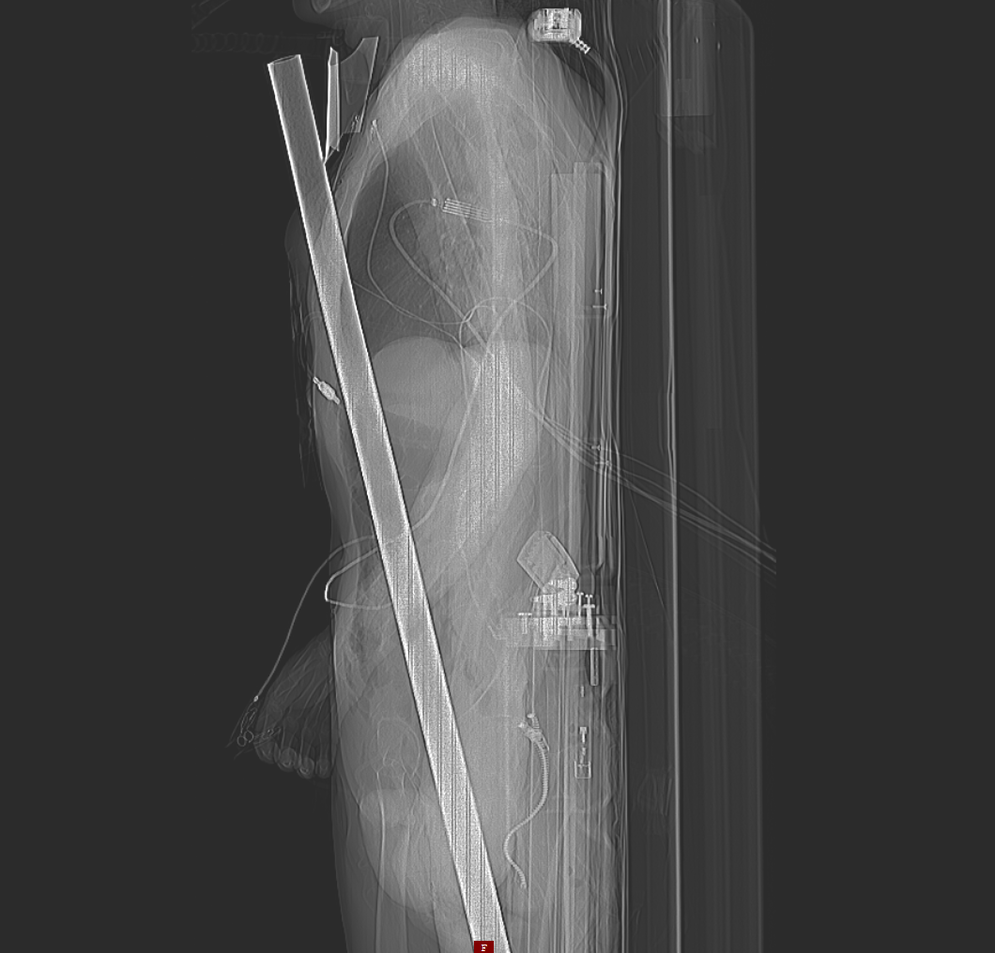

Frank Vaorin hatte unfassbares Glück im Unglück. Der 55-jährige Familienvater aus Cuxhaven stürzte bei Baumschnittarbeiten in seinem Garten von der Leiter, fiel vier Meter in die Tiefe und wurde von einer rostigen, mehr als einen Meter langen Zaunstange praktisch längs auf-spießt. Die Stange bohrte sich neben seinem After durch den Bauch, vorbei am rechten Dick-darm, an lebenswichtigen Gefäßen und der Leber, durch das Zwerchfell in den Brustkorb. Sie verschonte ebenso die Lunge, durchstieß einige Rippen und kam unterhalb des Schlüsselbeins wieder zum Vorschein.

Der Patient war samt der Stange mit dem Rettungshubschrauber in die Notaufnahme des Klinikum Bremen-Mitte gebracht worden. Zuvor hatte ihn die Feuerwehr auf seinem Grund-stück erst aufwendig vom Zaun freischneiden müssen. „Ich war die ganze Zeit bei Bewusst-sein“, erinnert sich Frank Vaorin. Sein Sohn Tom (21) hatte den Unfall im Garten direkt mitan-sehen müssen, alarmierte sofort die Rettungskräfte. „Ich weiß noch, wie ich dort auf der Stange hing, mit den Füßen in der Luft. Mein Sohn hatte mir schnell etwas unter die Füße geschoben, damit die Stange nicht noch weiter rutscht.“

Mediziner sprechen bei dieser Art von Unfall von einer Pfählungsverletzung. Kaum vorstellbar, dass die stabile Zaunstange einmal längs den Körper von Frank Vaorin durchbohrte, ohne ihn dabei lebensgefährlich zu verletzen. Die Teams aus Allgemein- und Viszeralchirurgie sowie Thoraxchirurgie befreiten Vaorin von der Stange.